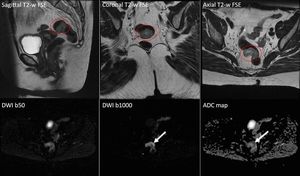

High resolution, multiparametric (anatomical and functional) MR Imaging of a colon adenocarcinoma. DWI provides information about tissue microarchitecture and can show the most aggressive regions of the tumour. Images courtesy of Christos Tsiotsios.